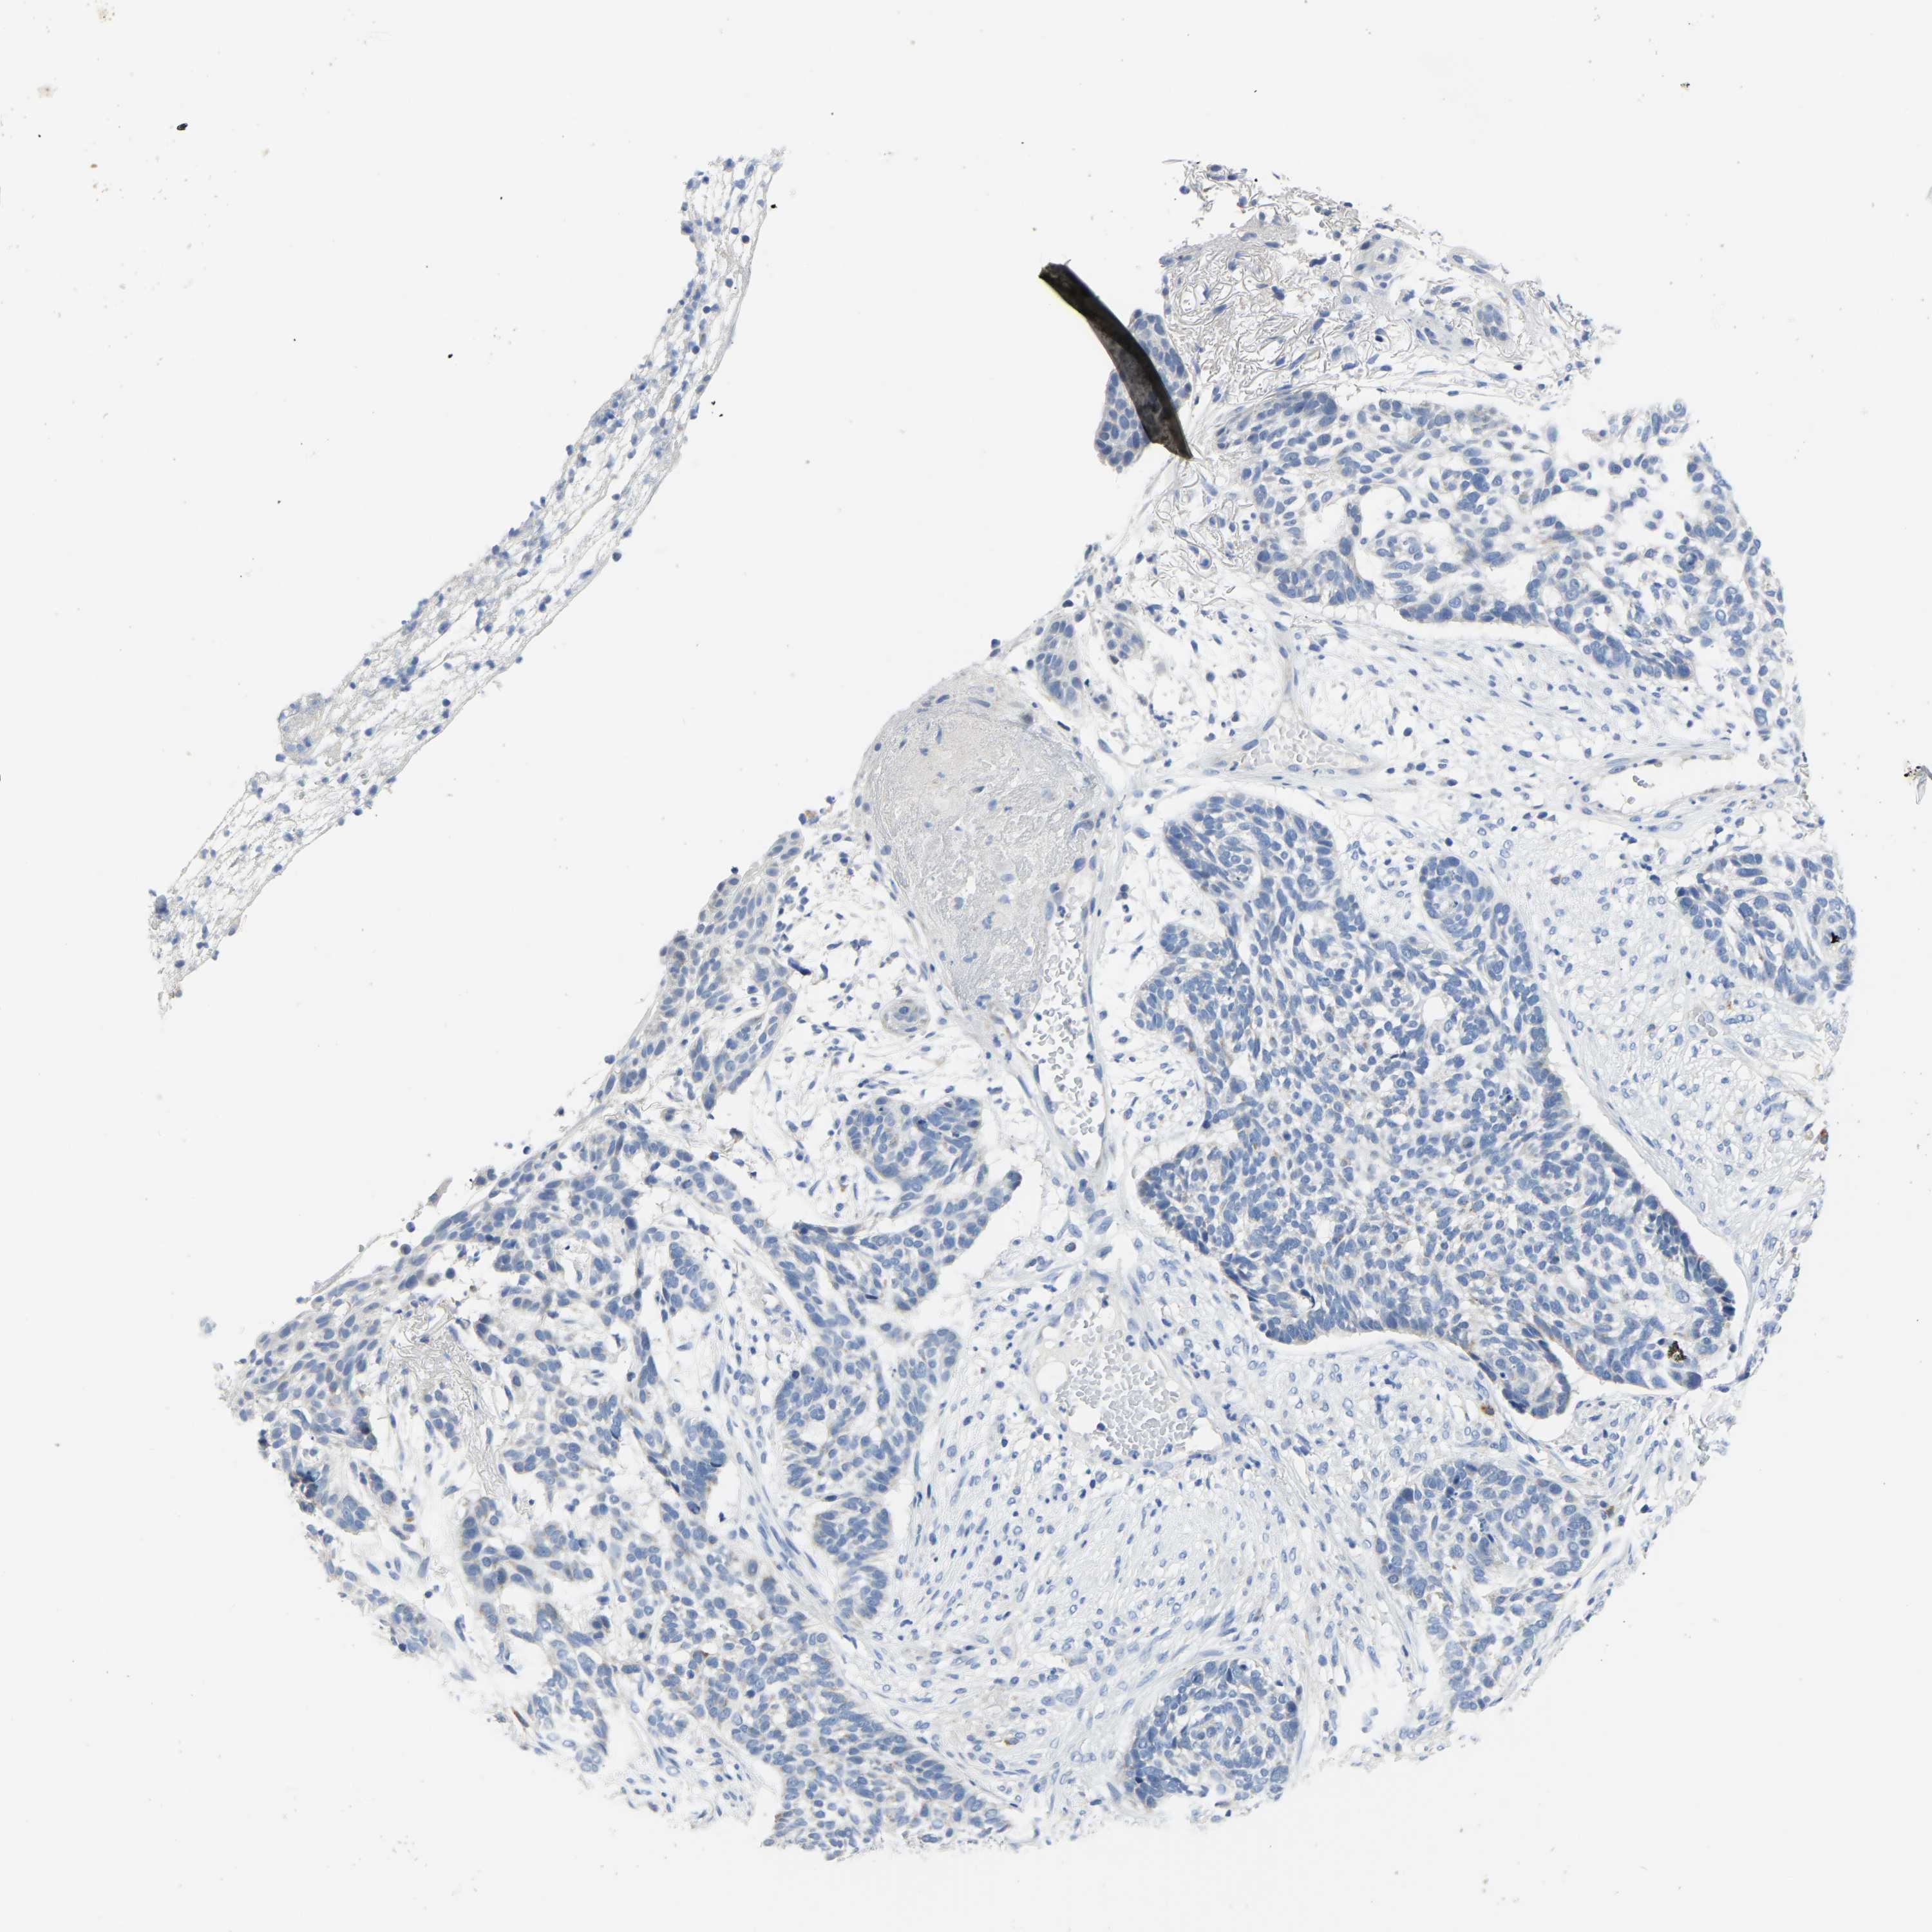

SKIN CANCER - Protein expressioni

A mouse-over function shows sample information and annotation data. Click on an image to view it in a full screen mode. Samples can be filtered based on level of antibody staining by selecting one or several of the following categories: high, medium, low and not detected. The assay and annotation is described here.

Each image is clickable and will lead to virtual microscopy that enables deeper exploration of all samples and also displays staining intensity scores, fraction scores and subcellular localization as well as patient and tissue information for each sample.

Antibody HPA018990

Basal cell carcinoma